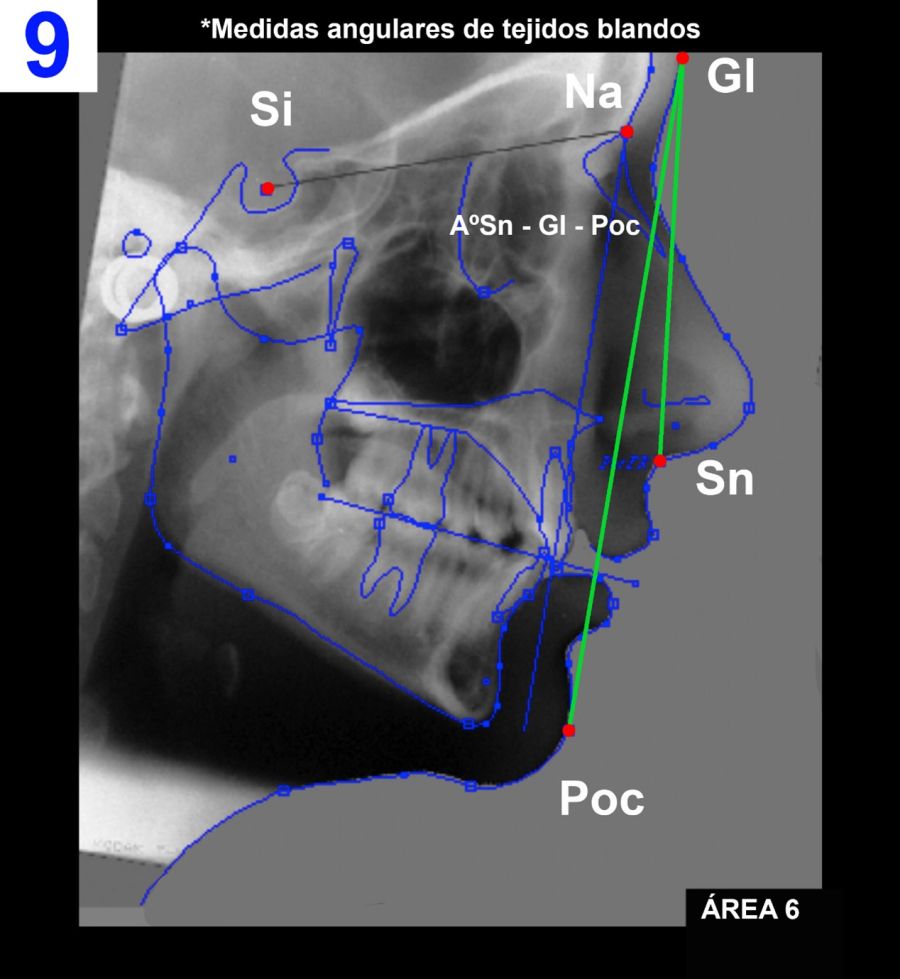

Área 6: Medidas angulares de tejidos blandos (Figura 9).

6.I) Sn – Gl – Poc.

Ángulo formado por los planos Gl – Poc y Gl – Sn.